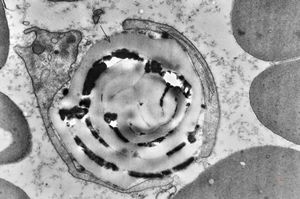

poxvirus - molluscum contagiosum